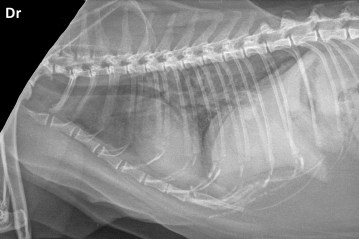

Signalement: chatte domestique calico stérilisée de 11 ans.

Histoire clinique: Anorexique et abattue depuis deux semaines, avec toux occasionnelle. Depuis 24-48 heures, ne file vraiment pas.